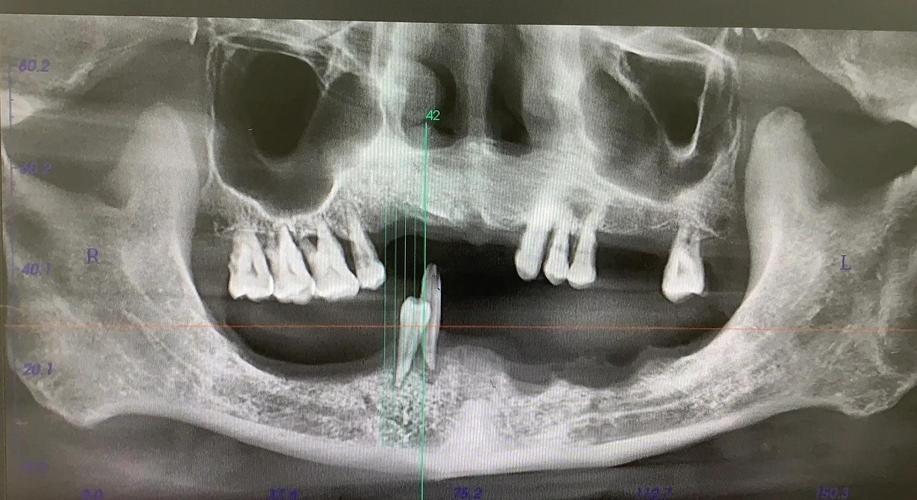

- 手术设备: 使用先进的影像设备(如CBCT)和手术导板可以提高精度。

- 咨询专业医生: 如果你考虑All-on-4,务必咨询经验丰富的种植牙医生,他们会根据你的具体口腔情况(CBCT评估)、全身健康状况、生活习惯等,评估你是否适合,并详细告知你预期的成功率、潜在风险和注意事项。